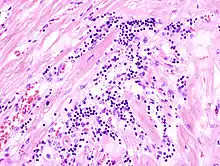

Virale Myokarditis

Mikro: Interstitielles lymphozytäres Infiltrat (kleine blaue Zellen), kaum Nekrosen.

![]() Virale Myokarditis bei Patient mit plötzlichem kongestiven Herzversagen, Autopsiepräparat, H&E. |

![]() idem. |